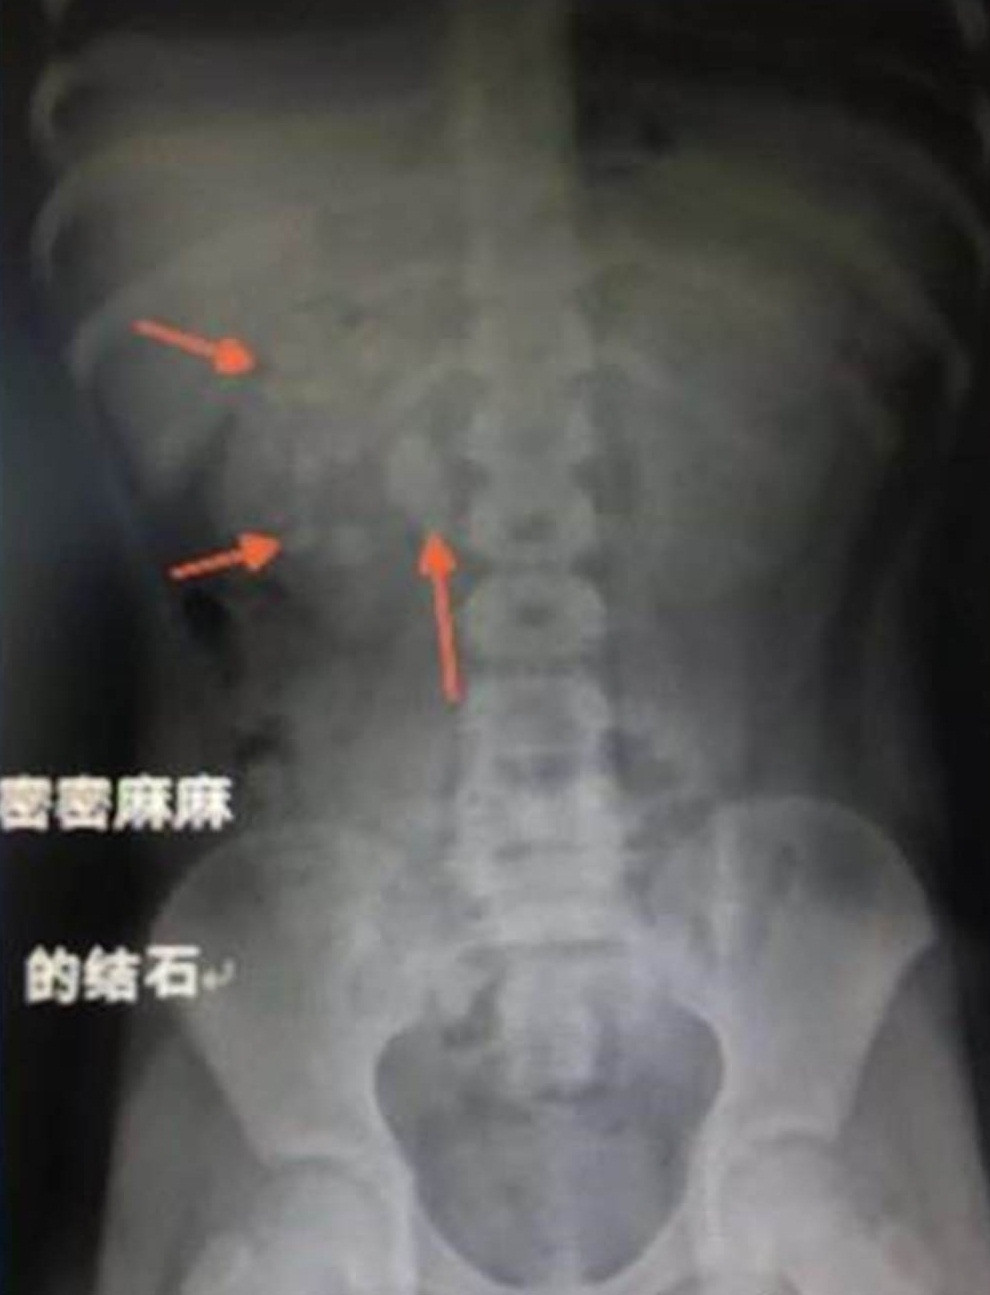

Sau khi cho cậu bé thực hiện một loạt cách xét nghiệm và kiểm tra, phim chụp X-quang của cậu bé cho thấy, thận của cậu bé có tồn tại sỏi ở cả hai bên, trong đó sỏi tập trung nhiều nhất ở thận phải.

Hòn sỏi lớn nhất có kích thước 2,5cmx2cm mắc kẹt ở chỗ nối giữa xương chậu gần thận phải và niệu quản, cũng chính vì vậy, niệu đạo bị chặn, gây ra tình trạng thận ứ nước, bị chướng hoặc sưng do nước tiểu tích tụ bên trong thận, dẫn tới hội chứng huyết tán tăng ure máu, buộc phải phẫu thuật ngay.

Sau khi phẫu thuật, các bác sĩ lấy ra được 56 hòn sỏi trong cơ thể của cậu bé, khiến toàn bộ gia đình cậu bé sợ hãi, choáng váng.